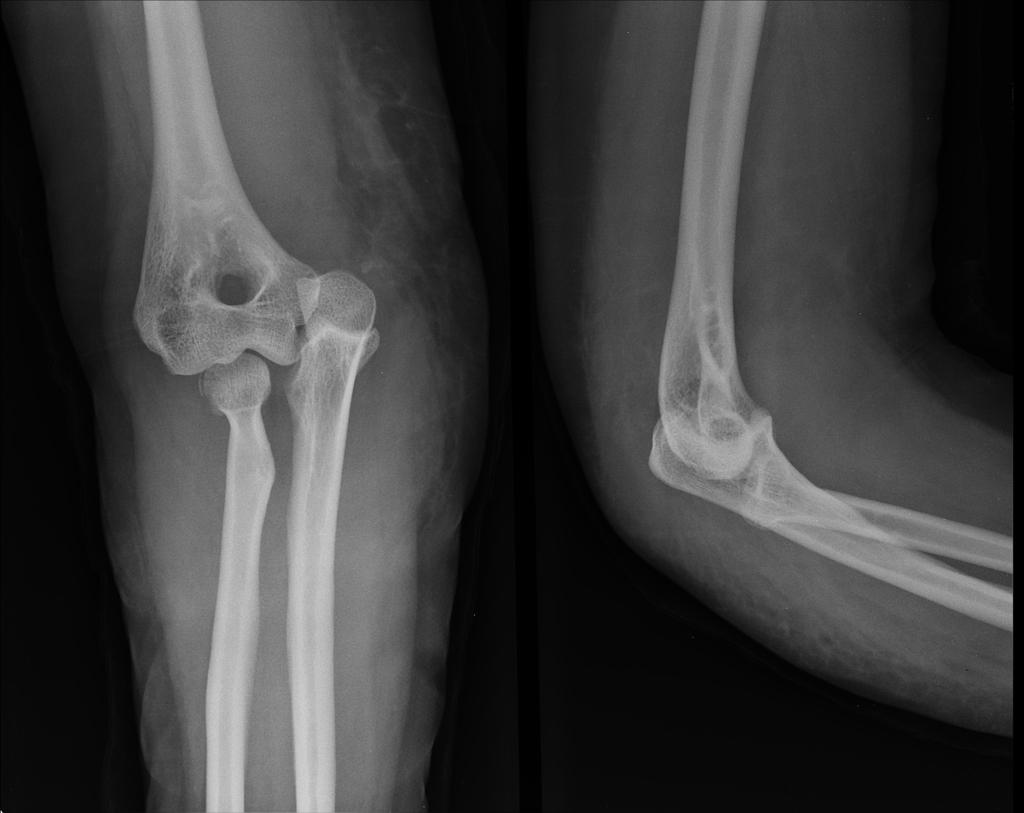

ELBOW DISLOCATION

Elbow dislocation occurs when the lower end of arm bone (humerus) and upper end of forearm bones (radius & ulna) are separated. Elbow dislocation can be partial (subluxation) or complete.

Elbow dislocation is also associated with fractures, ligament injuries and damage to blood vessels & nerves.